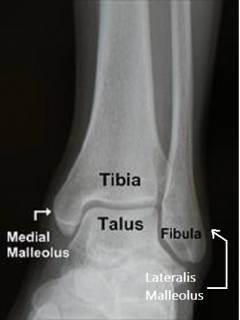

Рис. 1. Схематическое изображение костного компонента голеностопного сустава, вид спереди.

Кости голени (а именно лодыжки) как вилка охватывают таранную кость, образуя голеностопный сустав. Все поверхности костей, находящиеся внутри сустава называются суставными поверхностями. Суставные поверхности голеностопа покрыты гиалиновым хрящом, в полости сустава синовиальной оболочкой вырабатывается синовиальная (суставная) жидкость, ее функции:

Суставные поверхности голеностопного сустава (рис. 2)

A. внутренняя поверхность латеральной лодыжки, соединяется с латеральной лодыжковой поверхностью таранной кости;

B. нижний конец большеберцовой кости (свод голеностопного сустава);

C. внутренняя поверхность медиальной лодыжки, движения осуществляются относительно медиальной лодыжковой поверхности таранной кости;

D. блок таранной кости, соединяется с дистальными концами малоберцовой и большеберцовой костей;

E. латеральная и медиальная лодыжковые поверхности таранной кости.

Рис. 2. Голеностопный сустав, поверхности голеностопного сустава, распил во фронтальной плоскости.

Рис. 6. Рентгенограмма здорового голеностопного сустава, прямая проекция.

Tibia – большеберцовая кость, Talus – таранная кость, Fibula – малоберцовая кость, medialis malleolus – медиальная лодыжка, lateralis malleolus – латеральная лодыжка.